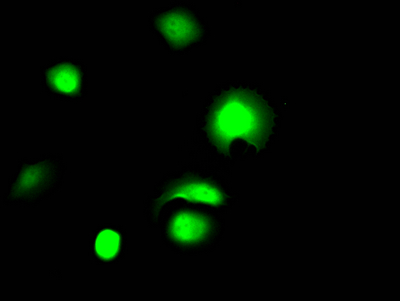

Immunofluorescence staining of MCF7 Cells with CSB-RA970289A0HU at 1:50, counter-stained with DAPI. The cells were fixed in 4% formaldehyde, permeated by 0.2% TritonX-100, and blocked in 10% normal Goat Serum. The cells were then incubated with the antibody overnight at 4℃. Nuclear DNA was labeled in blue with DAPI. The secondary antibody was FITC-conjugated AffiniPure Goat Anti-Rabbit IgG (H+L).